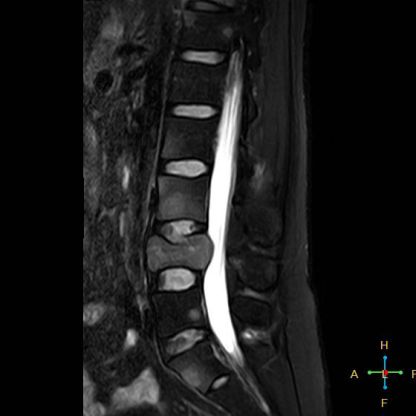

2 良性压缩性骨折 椎体形态:楔形、凹陷形。 椎体连续性病变(骨质疏松):新鲜、陈旧骨折并存。

椎间盘改变:椎间盘增厚呈双凸透镜状, 椎间盘疝入椎体, 形成许莫氏结节。

椎体后上角或后下角向后翘起, 呈尖突样突入椎管, 具有特异性,为其它原因的骨折所少见。

——良性压缩性骨折MR信号特点—— 良性骨折的修复过程:缺血性变化--修复(骨髓水肿、血流增加或充血现象)--修复近完成(血流恢复正常)--慢性期(脂肪组织再生)。 正常成人:椎体为黄骨髓,T1WI 、T2WI 均为高信号。 当骨髓内出现水肿时,T1 低信号, 与残余的正常骨髓形成明显对比,所以椎体压缩骨折后,MR 信号改变以 T1WI 上观察最好;而在常规 T2WI 图像上,病变骨髓的长 T2 高信号与正常骨髓脂肪信号差别较小,不易观察;T2WI 脂肪抑制技术对于突出显示骨折区长 T2 组织信号具有独特优势,对于判断椎体是否发生脂肪变及骨折是否愈合也有一定价值。 急性早期,椎体压缩,局部缺血,骨髓水肿,T1WI 不均匀低信号,T2WI 高信号,增强扫描无明显的强化。 随后,骨折部位开始修复,血流量增加,增强扫描可出现明显的强化,平扫信号无改变。 慢性期,骨髓内脂肪组织再生,T1WI 椎体内呈混杂高信号。

由于大多数外力轻微,椎体内多形成范围局限、移位不明显的骨折线,骨折线周围水肿亦多局限,因此,较少出现全椎体信号异常。

椎体后角回避现象:T1WI 椎体上部或大部呈低信号, 而后角信号不变。

椎弓根改变:由于旋转的扭力或是上下的压力造成椎体血流循环改变而致椎弓根的髓内水肿,使信号改变累及椎弓根,但椎弓根无变形或膨大。

所以,椎弓根的信号改变并非恶性骨肿瘤所特有,约20%~ 30%的良性压缩性骨折会出现椎弓根水肿而信号增高。 恶性压缩性骨折, 约有60%~ 80%出现椎弓根水肿及信号变化,而在椎弓根出现不正常信号的恶性压缩性骨折中, 约有50%~70%出现椎弓根膨大的现象,为其特异性, 可作为鉴别诊断的依据。 椎旁软组织肿块:最典型的表现为椎旁一薄环状异常信号带,因为椎体压缩时常继发椎旁软组织水肿与出血, 这一征象多见于单纯骨折, 病理性骨折少见。